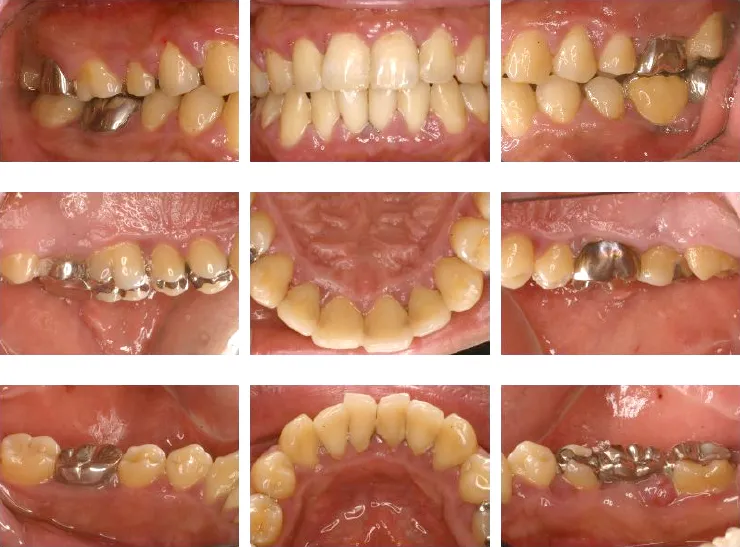

ご説明:説明は口腔写真とレントゲンを対比して、2つのモニタで表示した画面を見ながら行います。 また、口腔写真やレントゲン写真は 、画像を印刷してファイリングしてからお渡しするサービスを行っています。

この説明を通じてご自分のお口の状態を知っていただき、今後の治療の計画、メインテナンスの計画をお立てします。ムシ歯菌や歯周病菌の検査を必要とする方にはご説明し、ご了承を得てから実施します。| 16歳以上の予防歯科・費用と時間 | |